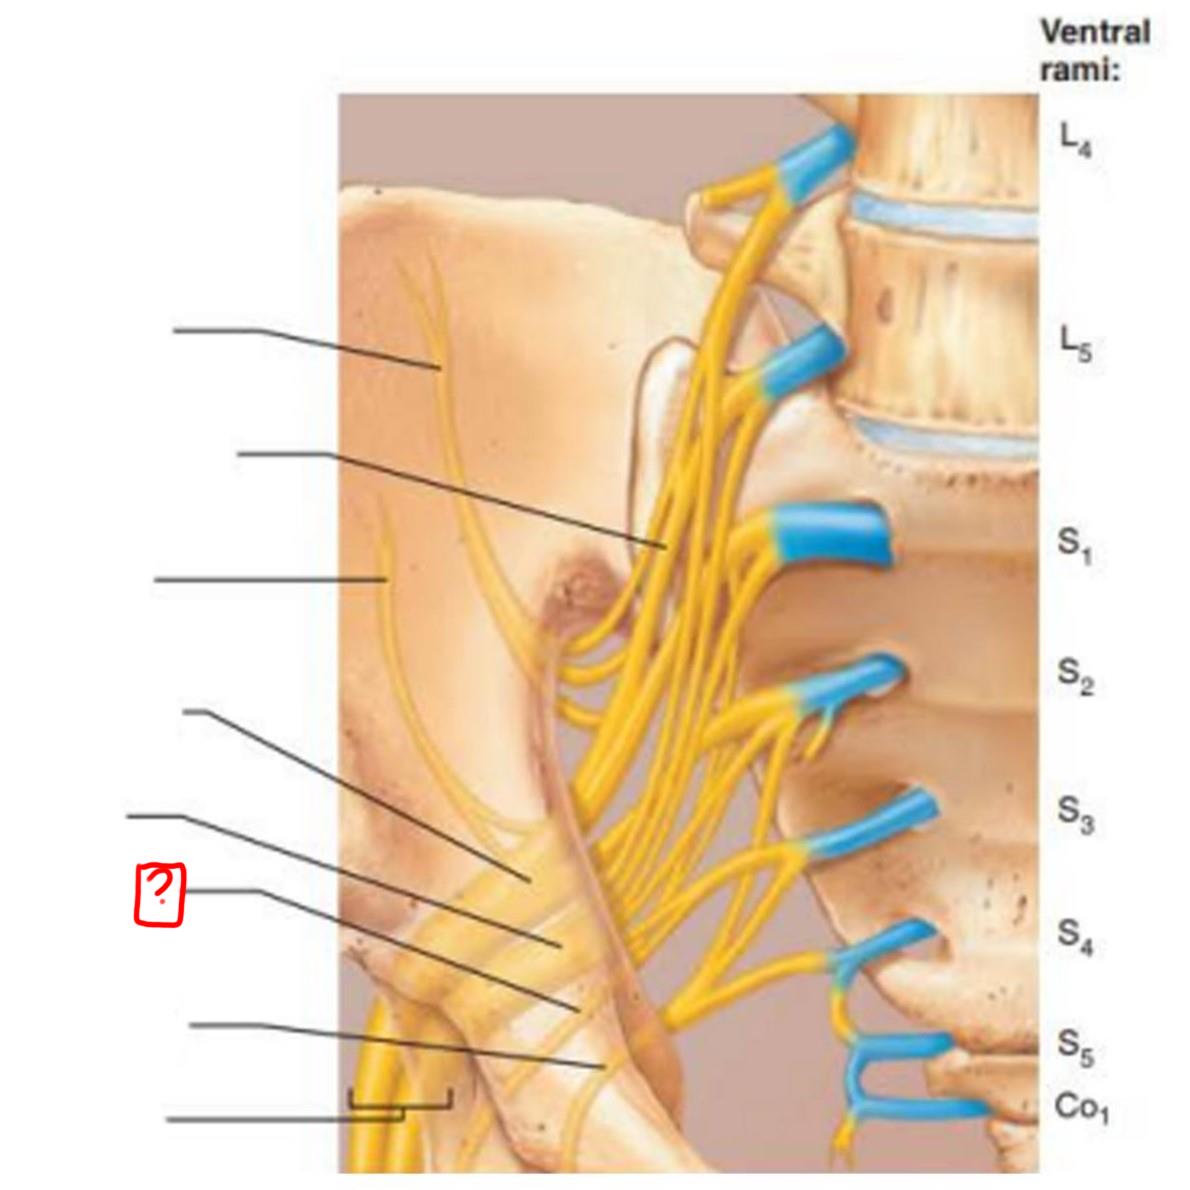

sacral nerves

S1-S5 (5 pair)

coccygeal nerves

Co1 (1 pair)

sacral plexus

L5-S4

lumbosacral trunk

superior gluteal

inferior gluteal

pudendal

sciatic

posterior femoral cutaneous

superior gluteal

lumbosacral trunk

inferior gluteal

common fibular

tibial

posterior femoral cutaneous